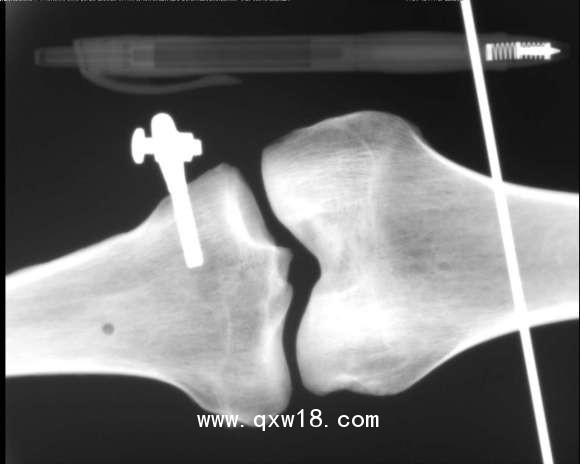

動物X光機

動物、海洋生物檢測儀,采用R160數(shù)字成像系統(tǒng)成像,?0.5微焦點射線管集約束散射線,數(shù)字成像,圖像清晰.儀器全數(shù)字化軟件操作功能;

XDX-DF160B型?動物、海洋生物檢測儀;主要針對動物,海洋生物、魚類檢測;同時還可用于:玩具、蟲草、斷針、金屬異物等檢測